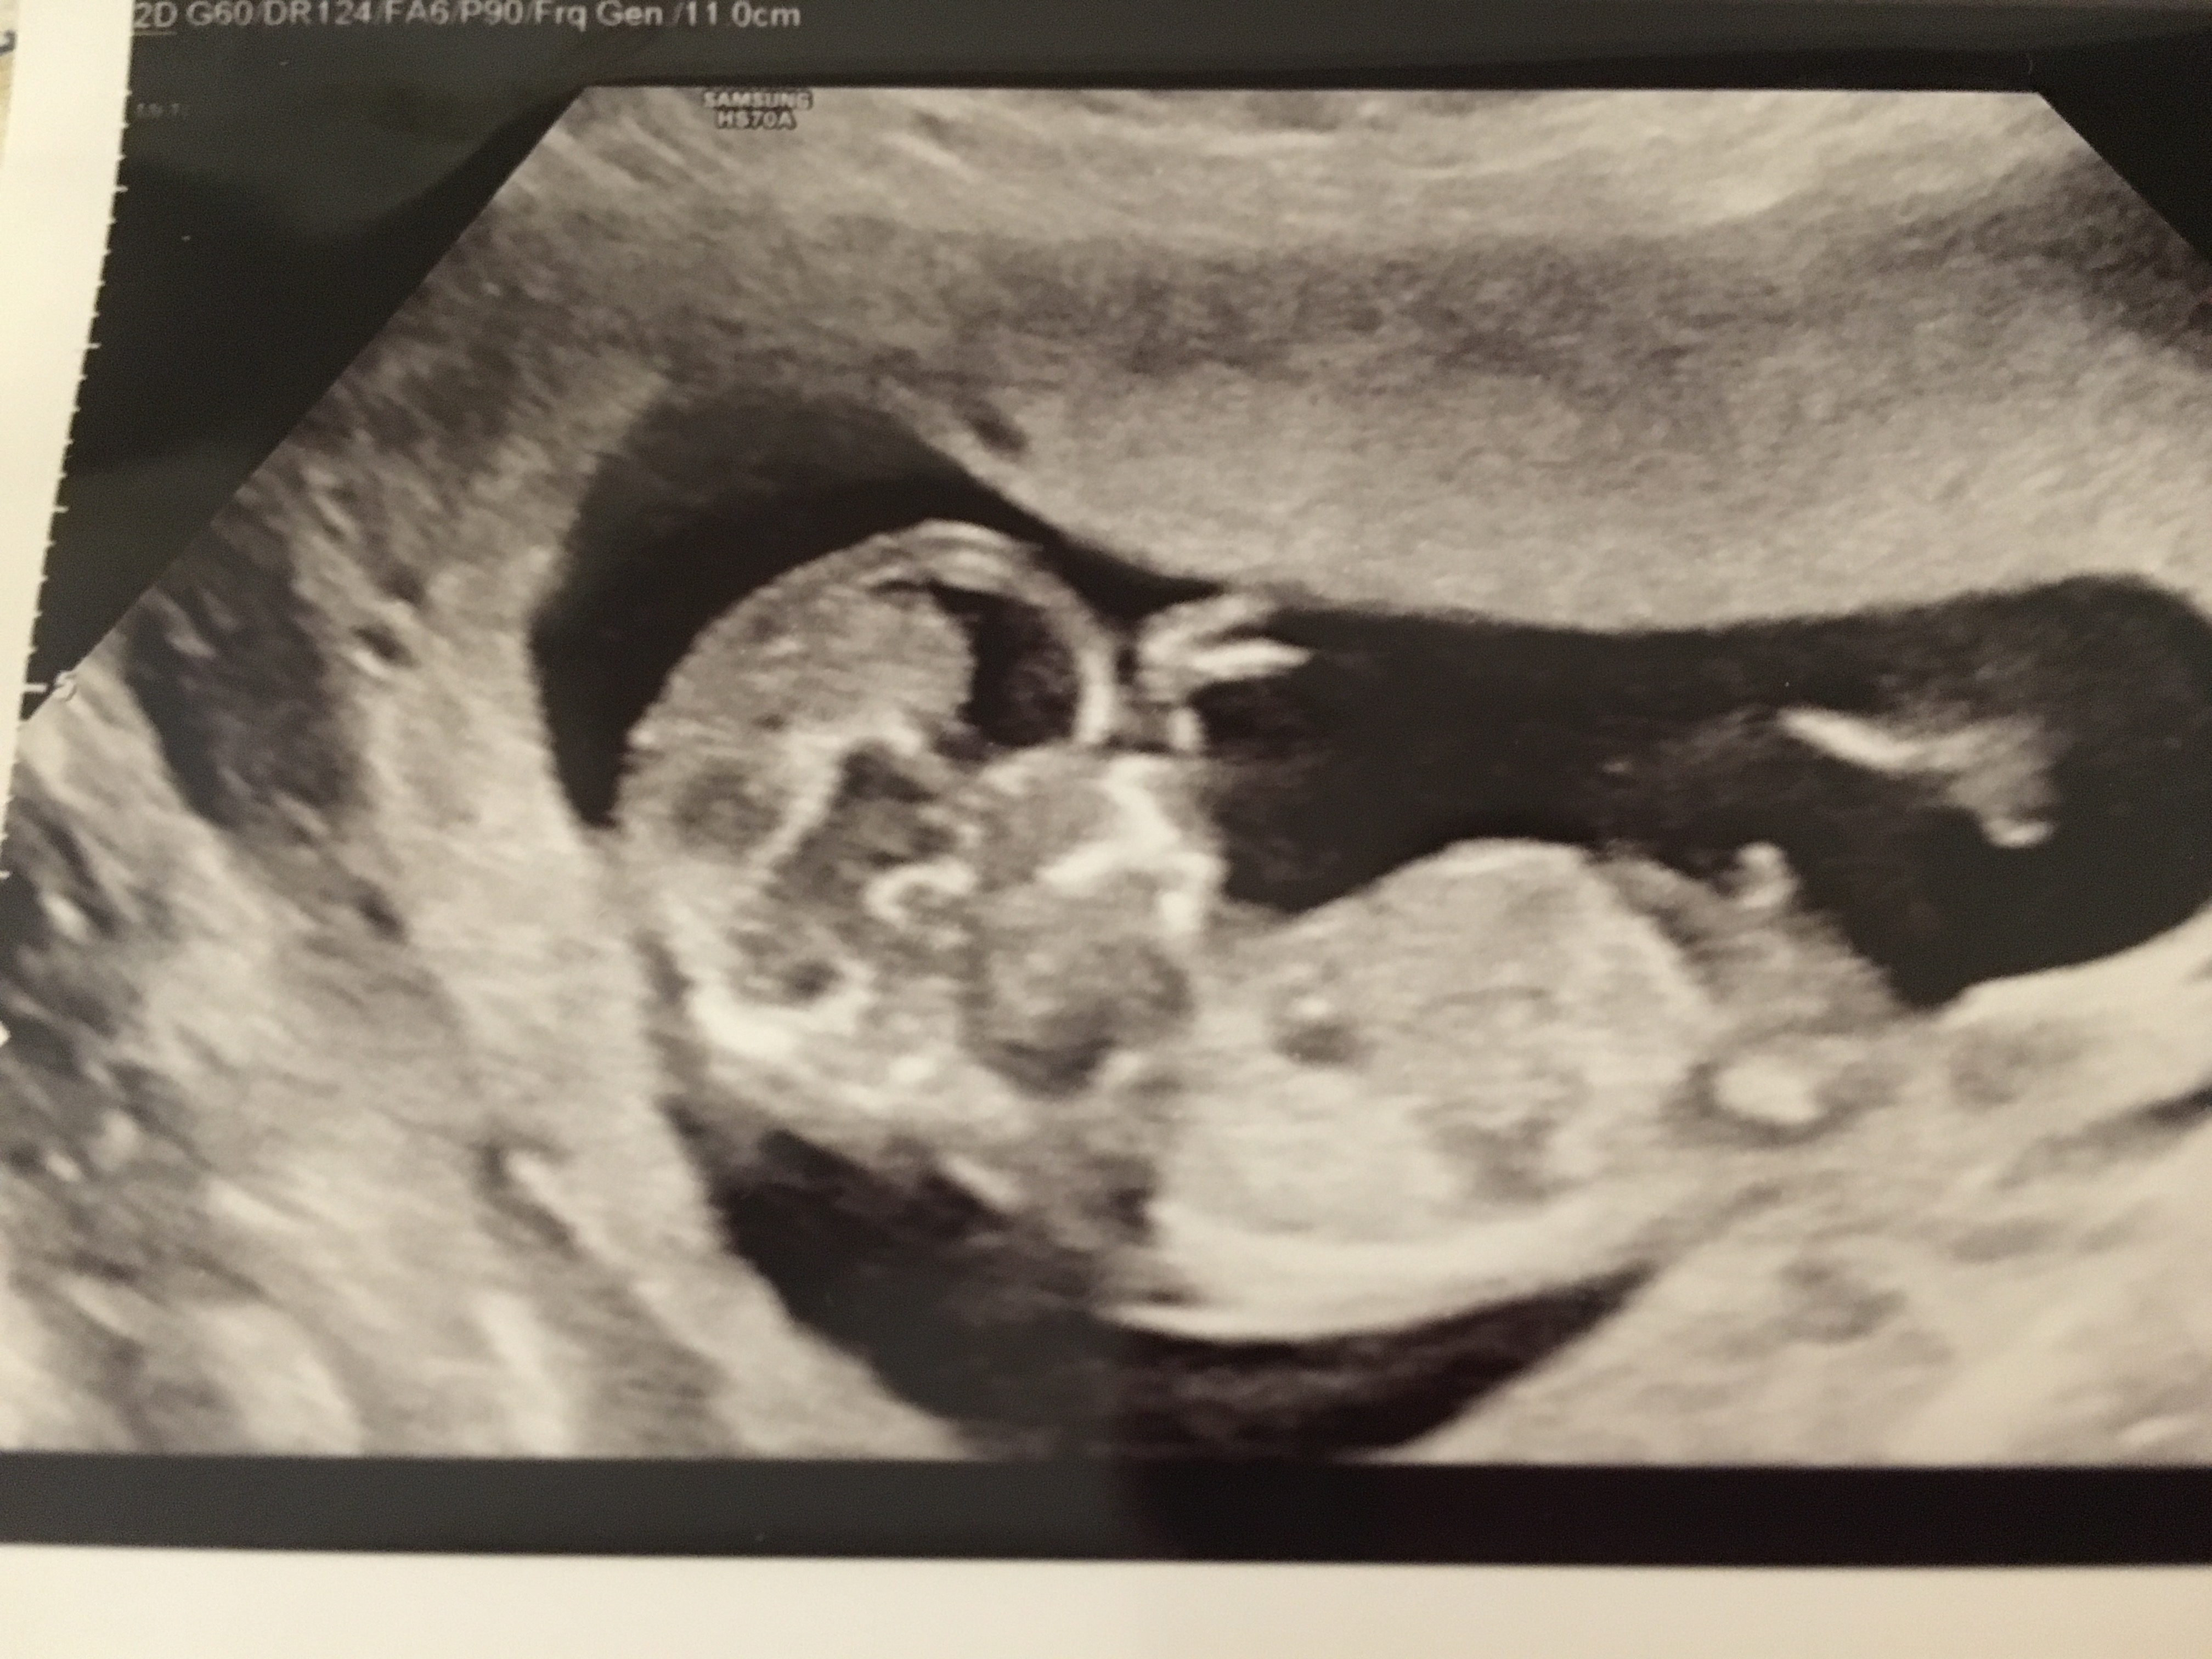

13w nub??

Not 100% sure if this is a nub or not. If it is, it looks boyish to me. All potty shots look clearly girl with 3 lines and no protrusion whatsoever. With my las pregnancy saw a clear penis protrusion at 13 weeks potty shot. Curious to get some feedback :) Attachment 33904Attachment 33905Attachment 33906

The first picture doesn't show a nub I think... looks a girl to me! Congrats

Very boyish :) The potty looks boyish too, boys can have 3 lines as well. I would say 99.9% boy.